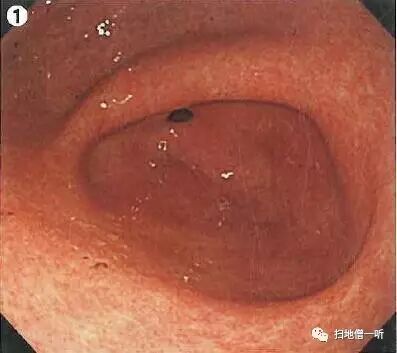

A:胃癌在图1。HP未感染胃癌。

背景粘膜光滑而有光泽,呈现均一的橘红色粘膜像,胃底腺区域RAC阳性,存在胃底腺息肉,以上均提示HP未感染。幽门前区大弯侧可见单发糜烂伴血痂附着,此病变为重点观察处。HP阴性的幽门前区经常会见到此类多发糜烂灶,故与癌的鉴别非常困难,鉴于此病例糜烂为单发,故需要进一步观察。

靛胭脂喷洒后病变中央可见边界清晰的小凹陷面,因良性炎性糜烂常常表现为周边平缓的移行。染色后征象怀疑癌,但仍不能以此确诊,故需进一步行活检。

最终病理诊断:

幽门前区大弯,O-IIc,4mm,sig,T1a (M),UL(-)